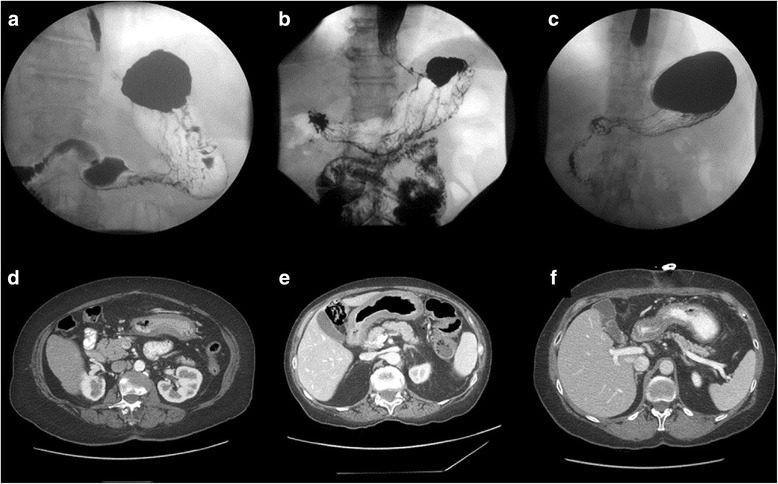

Typical symptoms of LP are dyspepsia, nausea, vomiting, and anorexia. Unfortunately, those symptoms are not reliable for establishing a timely diagnosis, as they usually present insidiously, and manifest only in an advanced stage. Available diagnostic instruments for this condition include endoscopy, endoscopic ultrasound (EUS), upper gastrointestinal contrast studies (UGI), computed tomography (CT) and 18-fludeoxyglucose (18-FDG) positron emission tomography (PET) scans, and magnetic resonance imaging (MRI) (Fig. 6).

Fig. 6.

Upper gastrointestinal imaging (a–c) and computed tomography (d–f) diagnostic features of linitis plastica in three different patients (patient 1: a, d; patient 2: b, e; patient 3: c, f)

CT allows for comprehensive staging of the tumor, and could give rise to reasonable suspicion when identifying a stomach with thickened walls, which presents with complete flattening of the mucosal folds or thickened folds even after distension [55, 65] (Fig. 6). Two studies focusing on the diagnostic yield of CT have described a specific enhancement pattern in LP patients [55, 65]. 18-FDG PET, by the contrary, may have scarce diagnostic significance, as poorly differentiated, diffuse, mucinous, and SRC carcinomas have all been reported to be low in 18-FDG uptake [66].